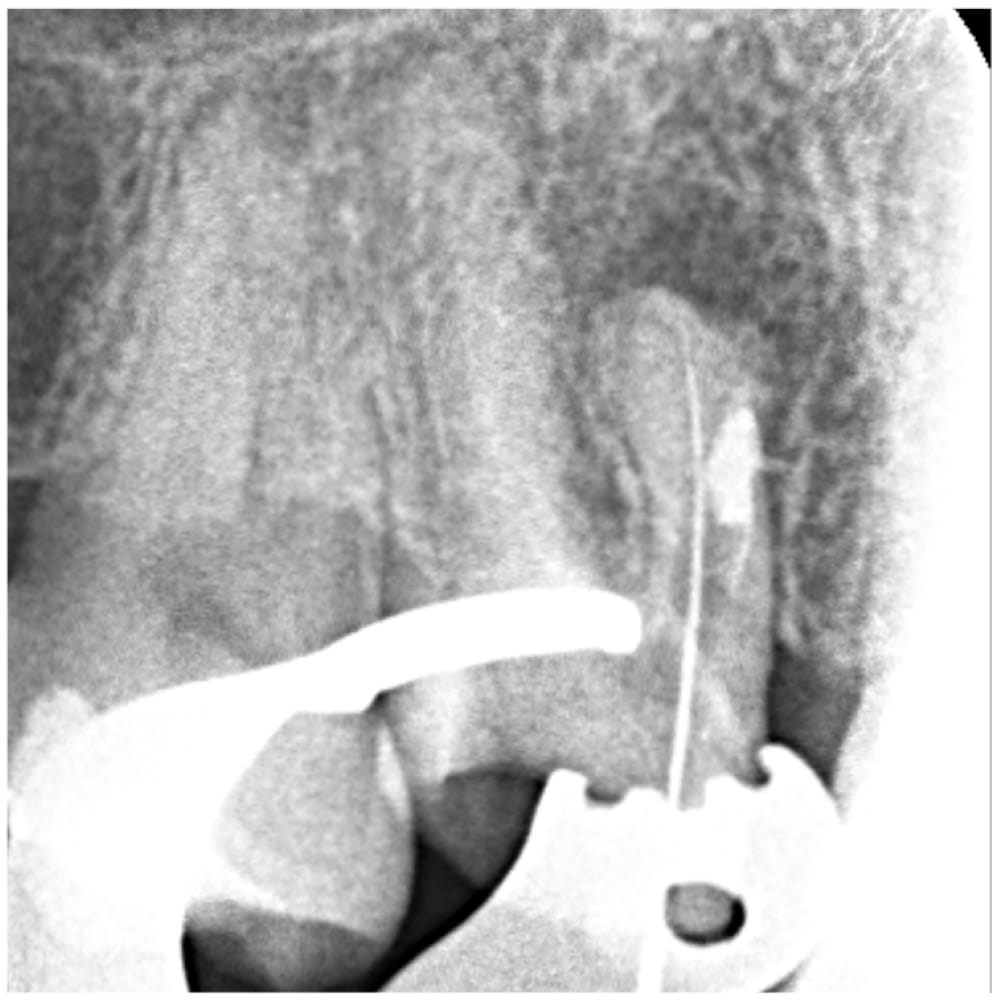

ステップ4

破折ファイルを除去し、本来のオリジナルの根管の方向や道筋が確認できました。これで、破折ファイルがあり清掃の妨げになっていた部位に対して、十分な感染源の除去が行えます。